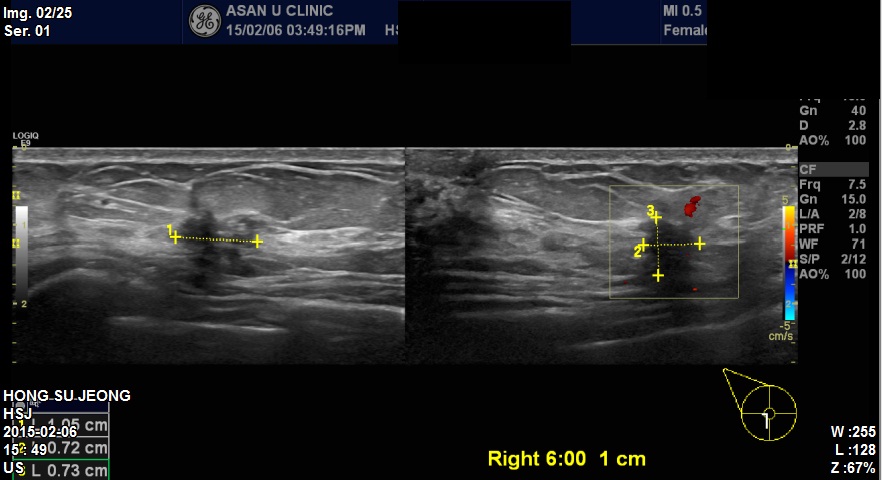

본원 내원하신 50대 환자분이십니다.

우측유방 6시방향에 1.05cm 혹 조직검사하였고

침윤성유관암 진단되었습니다. 감사합니다.